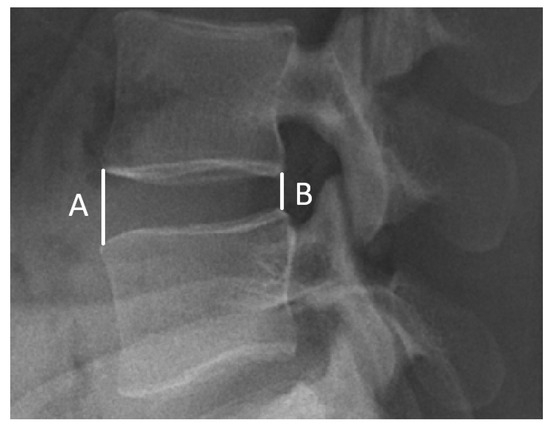

Thirdly, a radiographic assessment was conducted. For all cases studied, a lateral upright lumbar radiograph was obtained before and 6 months after the operations. To evaluate disc differences, the intervertebral disc height (IDH) was calculated preoperatively/postoperatively using Dabbs’ method [34,35]. The IDH was recorded as the average sum at the height of the anterior (A) and posterior (B) edge of the disc. The calculated formula was ((A + B)/2) (Figure 1). Average IDH values were compared among the three groups. Furthermore, the correlation between the clinical outcomes and changes in postoperative IDH was evaluated. All of the imaging calculations were performed by the same radiologist.

Figure 1.

Measurement of disc height. Calculation of disc height via Dabbs’ method (A + B/2).